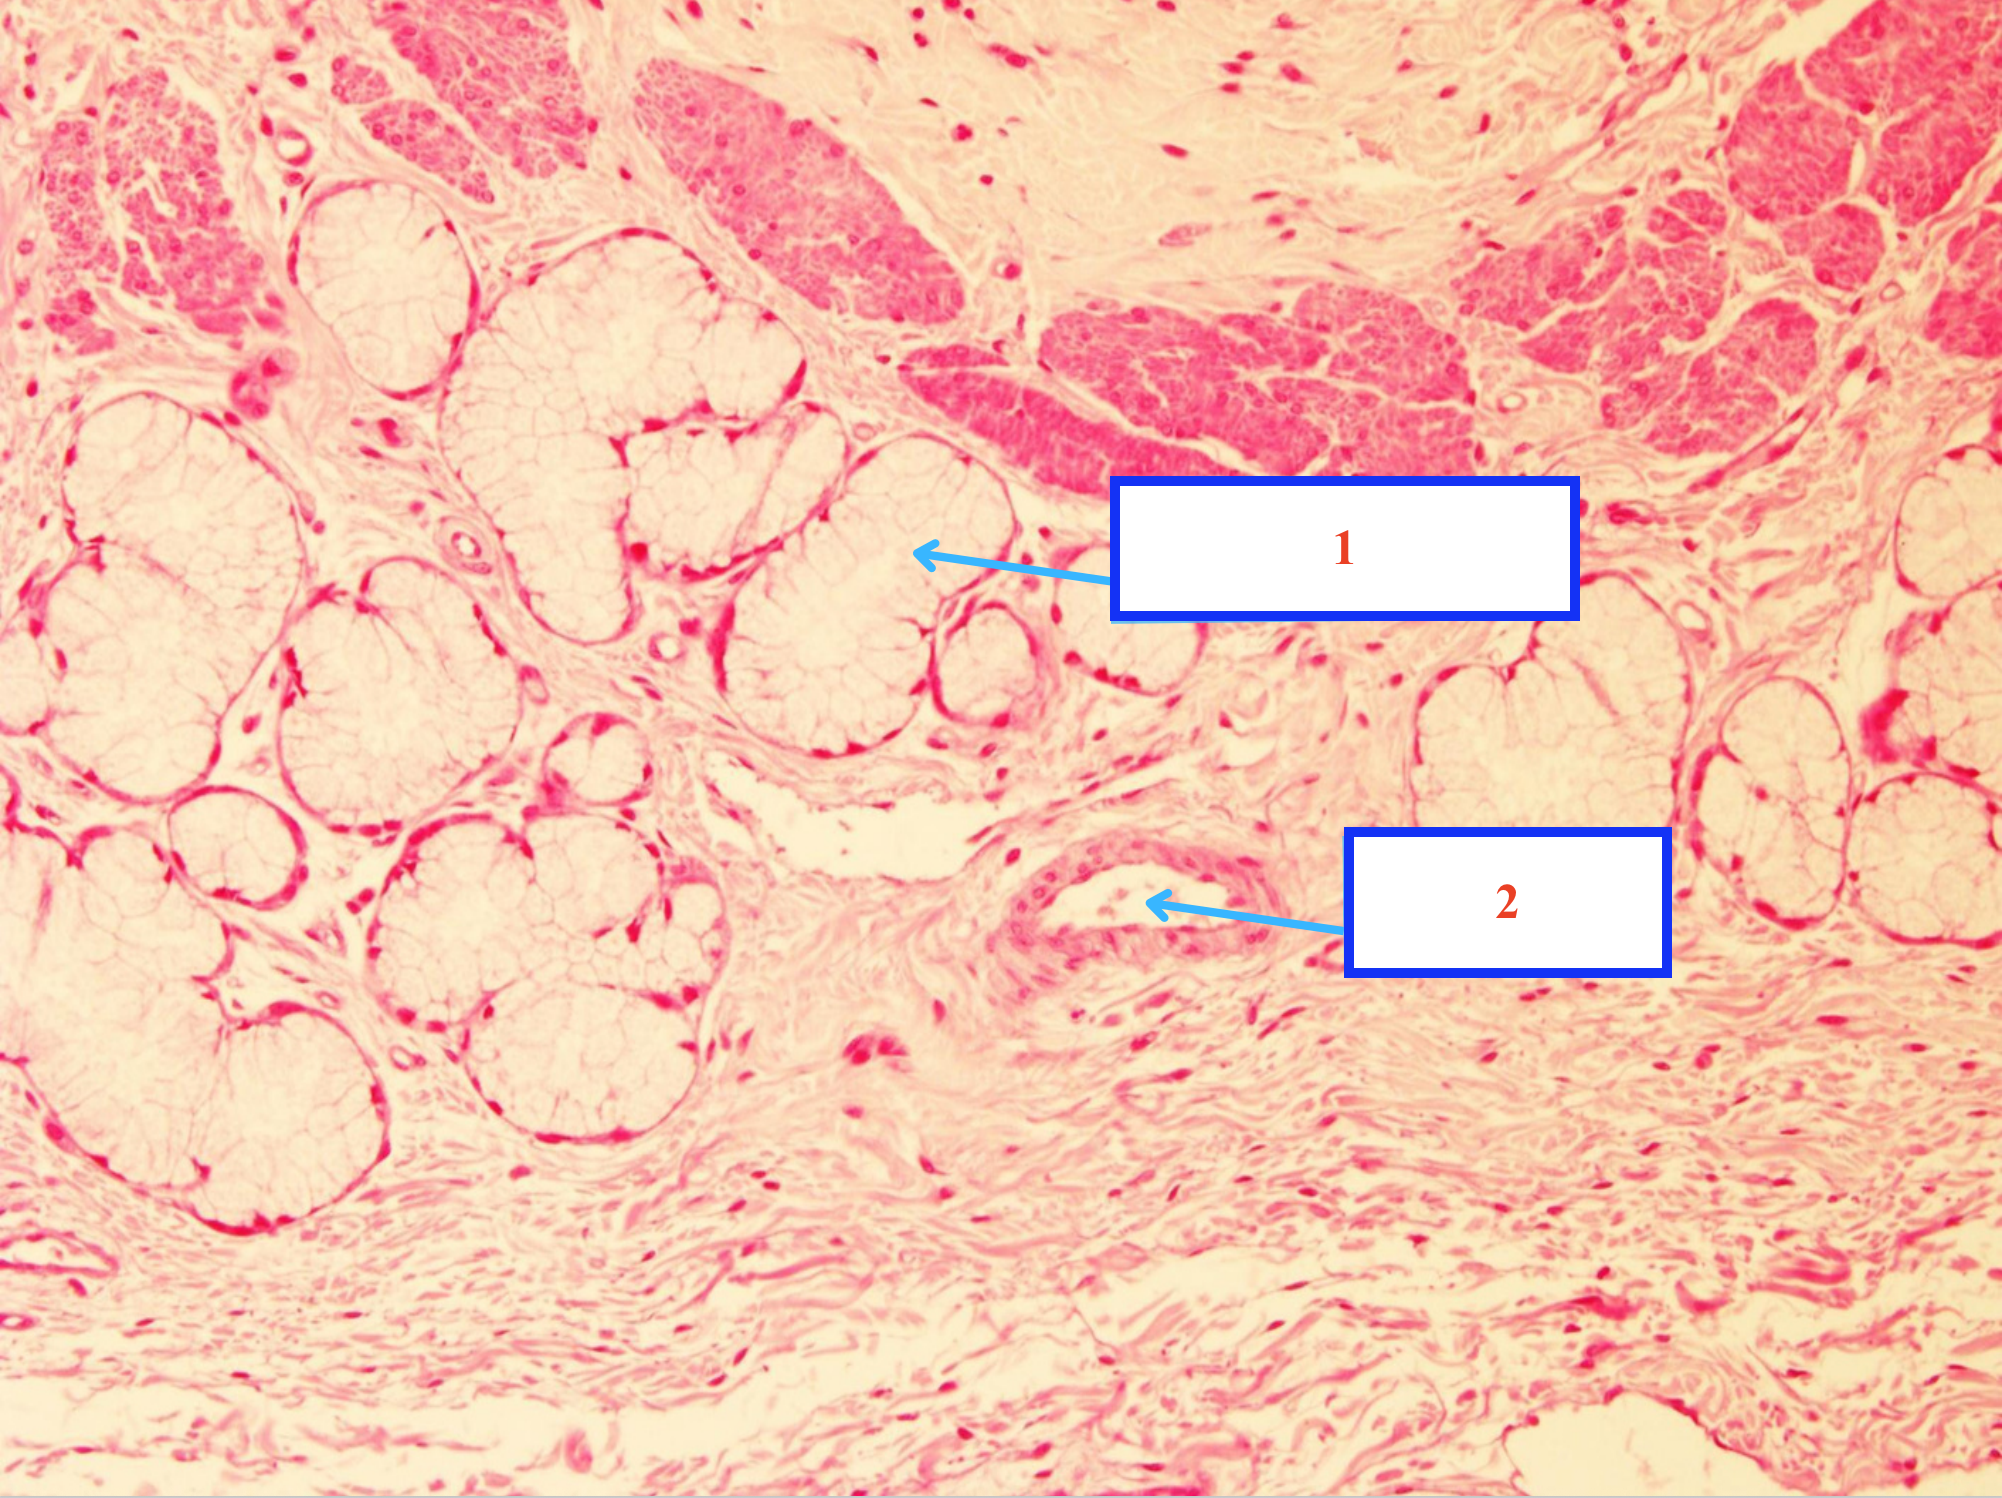

TUYẾN MANG TAI - TUYẾN DƯỚI HÀM:

Nang nước

Nang nhầy

Nang pha

Ống bài xuất trong tiểu thuỳ

Ống vân

Ống bài xuất gian tiểu thuỳ

Tiêu bản gì ?

Tuyến nước bọt

Cấu trúc gì ?

Nang tiết nhầy